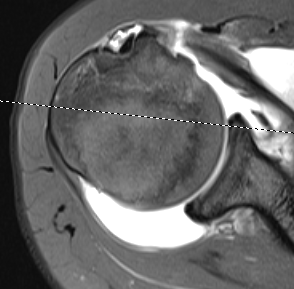

Supraspinatus atrophy

Tangent sign

- sagittal MRI

- line connecting superior coracoid and superior border scapular spine

- if supraspinatus muscle is below line, there is significant atrophy

- positive tangent sign / significant atrophy associated with larger tears / irrepairable tears

Negative tangent / no atrophy Positive tangent / significant supraspinatus atrophy